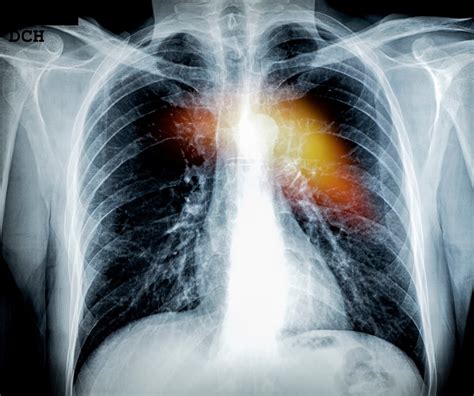

Secondary or metastatic bone cancer occurs when cancer cells from other parts of the body, such as the breast, prostate, or lung, spread to the bones. This is more common than primary bone cancer and can affect any bone in the body.

In cases of secondary bone cancer, symptoms may also include those related to the primary cancer, such as coughing or shortness of breath if the primary cancer is in the lungs.

• Imaging Tests: X-rays, CT scans, MRI scans, and bone scans can help identify bone abnormalities and determine the extent of the cancer.